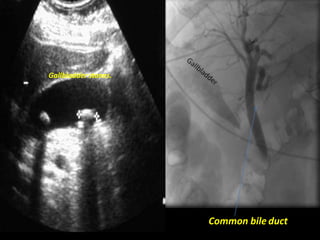

Common bile duct

Gallbladder stones.

Right common iliac vein.